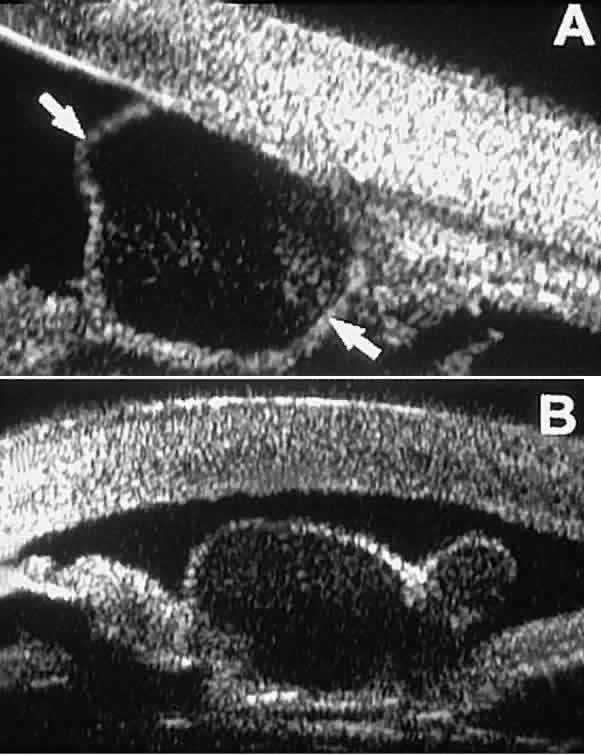

The role of UBM in the preoperative assessment of eyes with cataract is as yet unknown. In certain eyes, however, UBM may reveal features or abnormalities that could alter the ophthalmologist's surgical approach. Postoperatively, UBM can show the size and location of an intraocular lens (IOL) and the positioning of the haptics. A posterior chamber IOL appears on UBM as a highly reflective plate (corresponding to the lens optic) in the retropupillary plane with reverberation artifacts behind it (Fig. 17A). In contrast, an anterior chamber IOL appears on UBM as a sonoreflective plate located anterior to the pupillary plane (see Fig. 17B). In most eyes with a posterior chamber IOL, UBM can show whether the haptics are in the capsular bag (Fig. 18A), in the ciliary sulcus (see Fig. 18B), or in some other anatomic location12 (e.g., resting on the peripheral iris or secured with sutures to the sclera). The haptics are easier to locate if they are made of polymethyl-methacrylate than if they are made of proline because the former has a stronger reflectance.

Fig. 17. Composite UBM images of intraocular lenses. A. Posterior chamber IOL. B. Anterior chamber IOL.

Fig. 18 . Localization of posterior chamber IOL haptics by UBM. A. Haptic in capsular bag (arrow). B. Haptic (bright object just behind peripheral iris) in iridociliary sulcus.